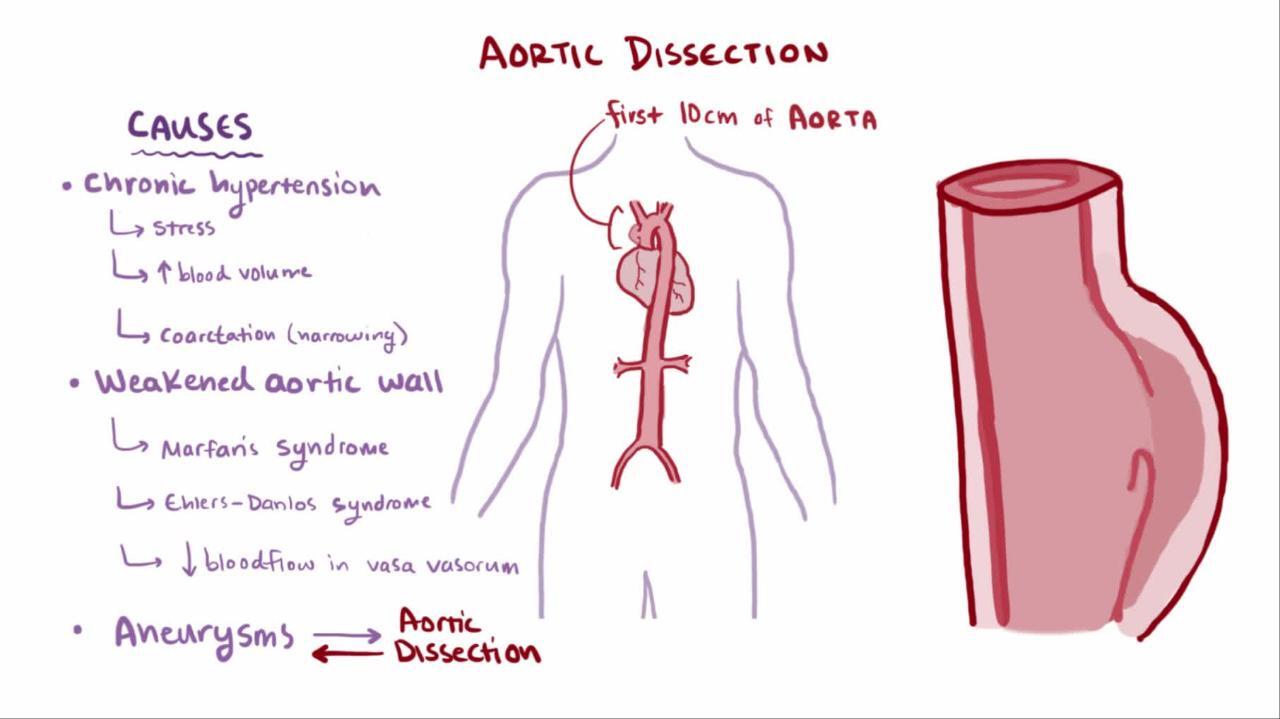

Aortic Dissection Without Chest Pain

Aortic Dissection Without Chest Pain

Aortic Dissection